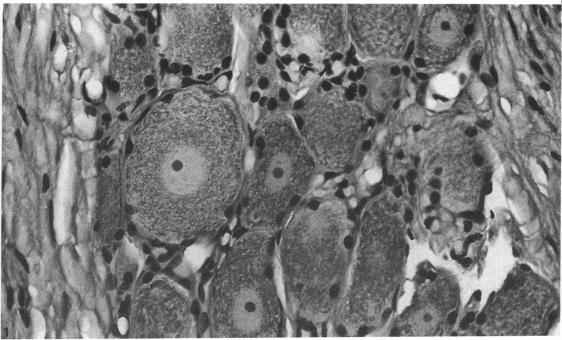

This investigation was designed to determine the change in cell numbers in the trigeminal ganglia following unilateral section of one of its peripheral branches. In 9 young adult cats, under general anesthesia, the inferior alveolar nerve was transected. In 3 of the animals the cut ends were reapposed and in the other 6 regeneration was blocked. After 15 weeks the trigeminal ganglia were removed, and the number of neurons present estimated by counting nucleoli in every third section. The counts were compared with those obtained from 3 unoperated control animals. The mean number of cells in the ganglia of control animals was 14,324 with no statistically significant difference between sides. There was no significant difference between counts from opposite sides of cats whose nerves were allowed to regenerate. In the animals in which regeneration was prevented the mean count on the operated side was 13,874 and on the unoperated 18,374. These differences were statistically significant and appeared to result from an increase in cell counts on the unoperated side rather than a reduction in the counts on the operated side. This may be explained by the presence of neurons with inconspicuous nucleoli in normal ganglia, which are stimulated to enlarge and become more prominent following peripheral nerve injury. This change could occur on both sides and would mask cell loss on the operated side and produce an apparent increase in the count on the unoperated side.

本研究旨在确定三叉神经节外周分支之一被单侧切断后细胞数量的变化。在9只成年幼猫中,在全身麻醉下切断下牙槽神经。其中3只动物的切断端重新对接,另外6只动物的神经再生被阻断。15周后取出三叉神经节,通过计算每第三切片中的核仁数量来估计神经元数量。将这些计数结果与3只未手术的对照动物的结果进行比较。对照动物神经节中的细胞平均数量为14,324个,两侧之间无统计学显著差异。神经被允许再生的猫的两侧计数之间也无显著差异。在再生被阻止的动物中,手术侧的平均计数为13,874个,未手术侧为18,374个。这些差异具有统计学显著性,似乎是由于未手术侧的细胞计数增加,而不是手术侧的计数减少。这可能是因为正常神经节中存在核仁不明显的神经元,在周围神经损伤后它们受到刺激而增大并变得更加明显。这种变化可能在两侧都发生,会掩盖手术侧的细胞损失,并导致未手术侧的计数明显增加。